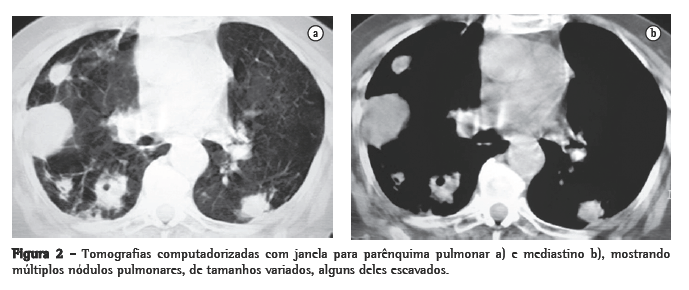

Foi realizada tomografia computadorizada (TC) do tórax, que confirmou a presença dos nódulos com tamanhos variados, sendo alguns escavados (Figura 2). Três amostras seguidas de escarro com pesquisa de bacilos álcool-ácido resistentes e fungos (coloração pela prata) foram negativas. A bacterioscopia (Gram) mostrou a presença de bactérias filamentosas nas três amostras colhidas de escarro, fortemente sugestivas de Nocardia spp., confirmada pela coloração de Ziehl- Neelsen, mostrando a característica resistência parcial à solução álcool-ácido (Figura 3).

Nódulos, massas escavadas, derrame pleural, pneumotórax, opacidades em vidro fosco e padrões intersticiais podem também ocorrer.(1,4,5,11) Alguns estudos mostram que, em pacientes HIV positivos, existe um percentual maior de lesões escavadas.(8) A consolidação alveolar nos lobos superiores é muitas vezes confundida com tuberculose pulmonar.(6) Embora as alterações vistas na TC sejam ­semelhantes às das radiografias convencionais, a TC é superior na demonstração da exata localização e extensão das lesões, assim como na diferenciação entre lesões pulmonares e pleurais.(5) No caso relatado, a paciente apresentava imagens nodulares de tamanhos variados, disseminadas por ambos os pulmões, e algumas delas escavadas.